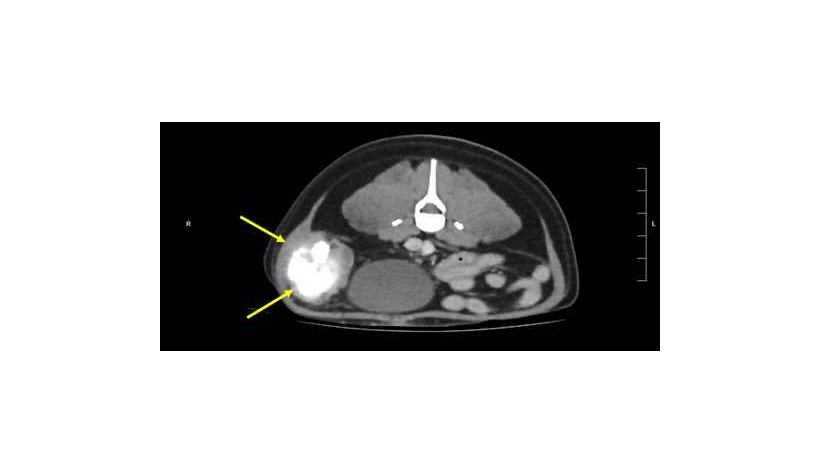

Cette étude* décrit la présentation clinique, le traitement et l'évolution de 4 chiens et 1 chat atteints de sarcome associé à un gossypibome** dans des centres de référés au Royaume-Uni, en Europe, Amérique du Nord et Australie à partir de dossiers clini...